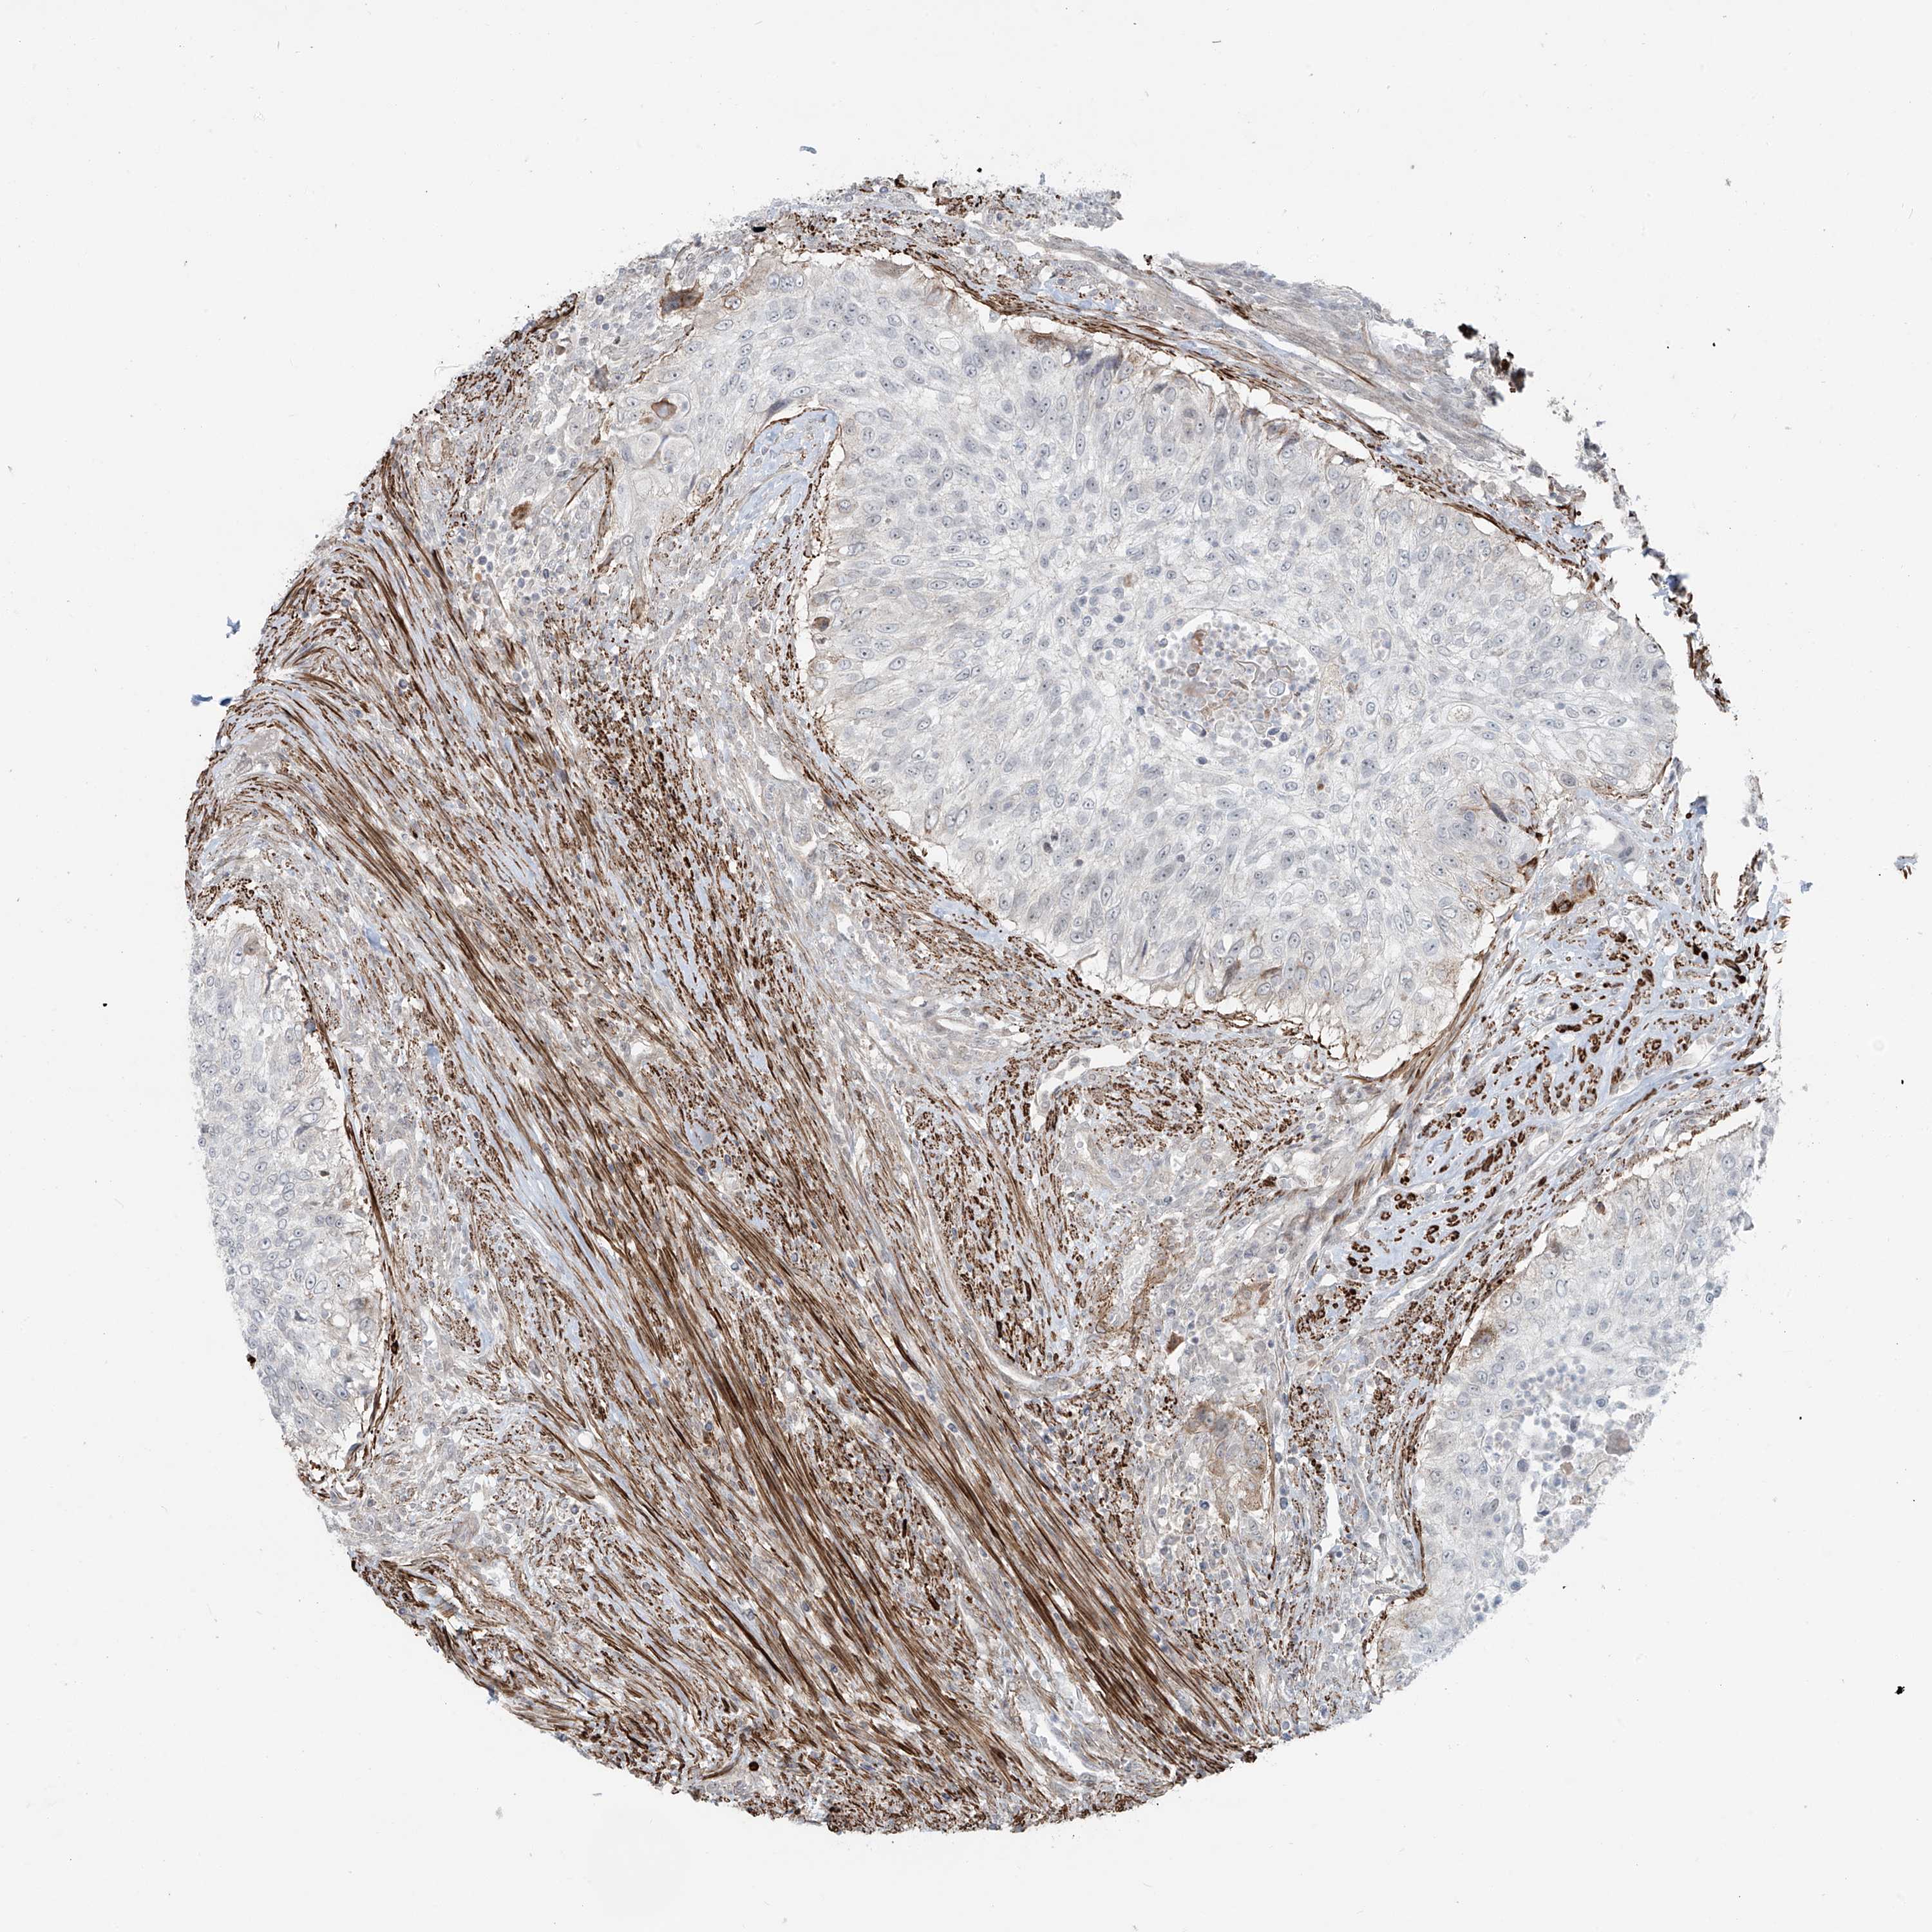

UROTHELIAL CANCER - Protein expressioni

A mouse-over function shows sample information and annotation data. Click on an image to view it in a full screen mode. Samples can be filtered based on level of antibody staining by selecting one or several of the following categories: high, medium, low and not detected. The assay and annotation is described here.

Note that samples used for immunohistochemistry by the Human Protein Atlas do not correspond to samples in the TCGA dataset.

Antibody stainingi

Antibody staining in the annotated cell types in the current human tissue is reported as not detected, low, medium, or high, based on conventional immunohistochemistry profiling in selected tissues. This score is based on the combination of the staining intensity and fraction of stained cells.

Each image is clickable and will lead to virtual microscopy that enables deeper exploration of all samples and also displays staining intensity scores, fraction scores and subcellular localization as well as patient and tissue information for each sample.

Antibody HPA035593

Staining

High

Medium

Low

Not detected

Intensity

Strong

Moderate

Weak

Negative

Quantity

>75%

75%-25%

<25%

None

Location

Nuclear

Cytoplasmic/membranous

Cytoplasmic/membranous,nuclear

Urothelial carcinoma, High grade

Urothelial carcinoma, Low grade